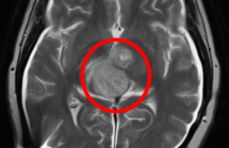

南開大學化學學院陳悅教授課題組原創(chuàng)新藥ACT001臨床試驗結果公布

【制藥工業(yè)】 南開大學化學學院 2021-07-23

ACT001針對惡性膠質(zhì)瘤這個世界醫(yī)學難題,其臨床試驗結果由中外醫(yī)生先后公布于美國臨床腫瘤學會ASCO與神經(jīng)腫瘤學會SNO...